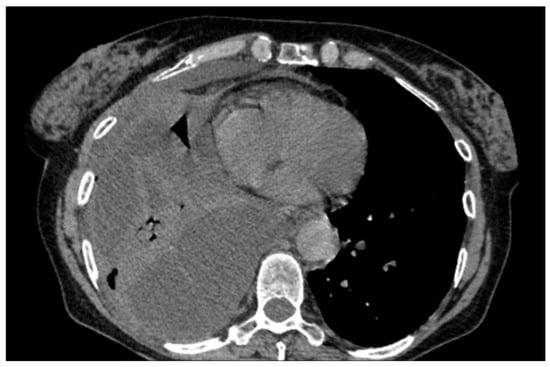

A 60-year-old Caucasian man was admitted to our hospital with a history of worsening pain at the base of the right hemithorax and feeling generally unwell for over one month. The patient’s past medical history included coronary heart disease, with a percutaneous coronary intervention in 2014. He smoked a half-pack of cigarettes per day for 40 years and had no history of respiratory disease. The CT chest scan showed a fluid collection in the medium–lower parts of the right hemithorax with thickened walls and contrast enhancement (Figure 5). This collection appeared in continuity with further smaller fluid collections with thickened walls, contrast enhancement, and confluence and caused the complete atelectasis of the middle and lower lobes and the partial atelectasis of the upper lobe, as well as middle and inferior lobar bronchus occlusion.

Figure 5. Chest CT scan of the mediastinal window in the coronal (A) and axial (B) plane, showing fluid collection in the medium–lower parts of the right hemithorax (maximum axial dimeters of 19 × 13 cm; craniocaudal extension of 16 cm) with thickened walls and contrast enhancement. There is also a complete atelectasis of middle and lower lobes and partial atelectasis of the upper lobe.